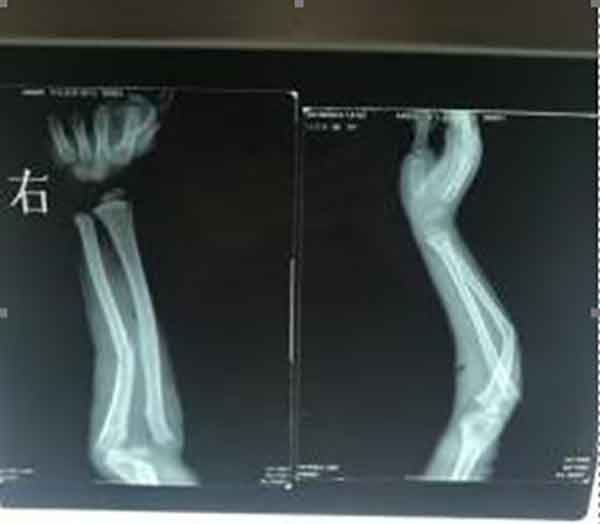

付天宇,男,7岁,系游家镇金字村付家冲人。2018年9月24日下午2时许,一次狮子山旅游在山顶游乐场摔伤。老科协医院35591影片号所示:右尺骨中上段粉碎性骨折、右肘关节尺桡骨撕脱性骨折,右尺骨中段不规则骨折,可见骨片分离等多处骨折征象。当时去医院入诊,医师建议去上级医院治疗。后经人介绍找到了梅山水师骨科医生曾令先。经阅片和临床诊断,医者先安慰患者家属,再准备外固定所需材料,然后给患者一次性复位,后石膏外固定。固定术后再去医院拍片复查。服用祖传中草药。拆外固定时拍片复查。26天,付天宇右手恢复正常。家长、患者、游乐场老板非常满意。同时,从来不牟患者利益,付天宇多处骨折,含材料费、治疗费仅花1200元。付天宇监护人联系电话13319687783